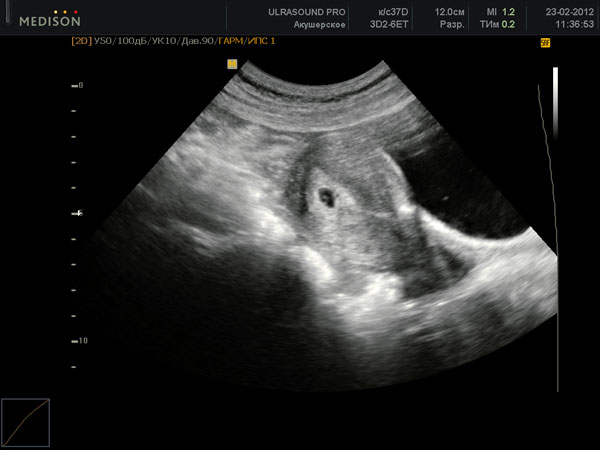

Если врач назначил также УЗИ, то оно, даже несмотря на такой ранний срок беременности, уже покажет, как растет и развивается эмбрион и какие изменения происходят в организме женщины.

УЗИ плода на 6 неделе